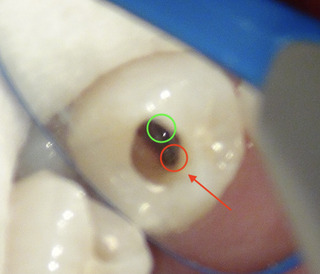

口腔内を見た状態 キレイにレジンが詰められていますね

上から削っているところ なかなか根管口が見つからないので、レントゲンで位置を確認。

やはりありました。もう一つの根管。

1根じゃなく2根管だったのね。

赤丸が2根管目。

治療する時は全てマイクロスコープを使用しています。

その方が今回のように根管が隠れているのも見つけやすいですし、

虫歯の取り残しもなくなりますし、精度の高い治療が行えます。